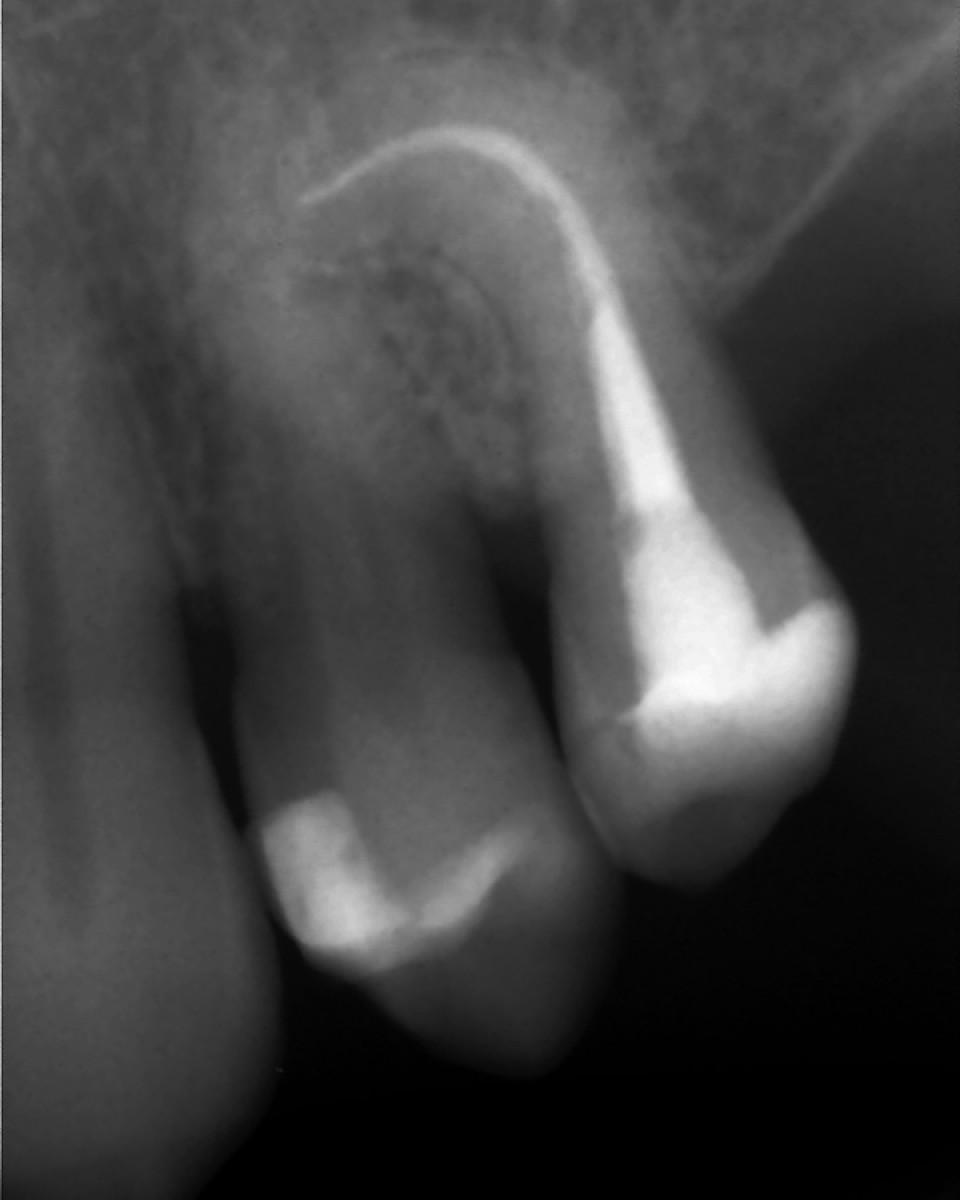

These files are, in fact, mainly in the martensite phase in body temperature (Shen et al, 2011). When the material is in its martensite form, it is soft, ductile, without shape memory and more favourable fatigue resistance than an austenitic microstructure (fig 1, 2, 3).

In 2015 Coltene introduced the new generation of Hyflex files called EDM, referring to the specific design of the file obtained by using an innovative manufacturing process called Electrical Discharge Machining. The EDM process results in a file that has an increased surface hardness cutting efficiency, is extremely flexible, fracture resistant and thanks to controlled memory properties, can follow the anatomy of the canal reducing the risk of ledging, transportation and perforation (Pedullà et al 2015). The sequence is very simple. There is an Orifice Opener #25 in diameter and 12% taper (25.12), used to relocate and enlarge the orifices of the canals. The glide path file (10.5) is used to create a smooth path for the OneFile (#25 variable taper from 8 to 4%) used as the last file (figure 4).

The extreme flexibility  and fatigue resistance of these files, combined with the lack of restoring force, render them ideal to be used for the instrumentation of highly curved and complicated canals (figure 5).